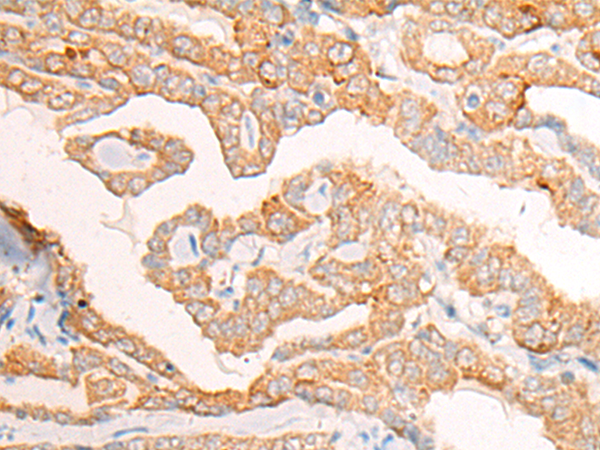

The image is immunohistochemistry of paraffin-embedded Human thyroid cancer tissue using 46974(COX15 Antibody) at dilution 1/25. (Original magnification: ?00)

,

The image is immunohistochemistry of paraffin-embedded Human esophagus cancer tissue using 46974(COX15 Antibody) at dilution 1/25. (Original magnification: ?00)